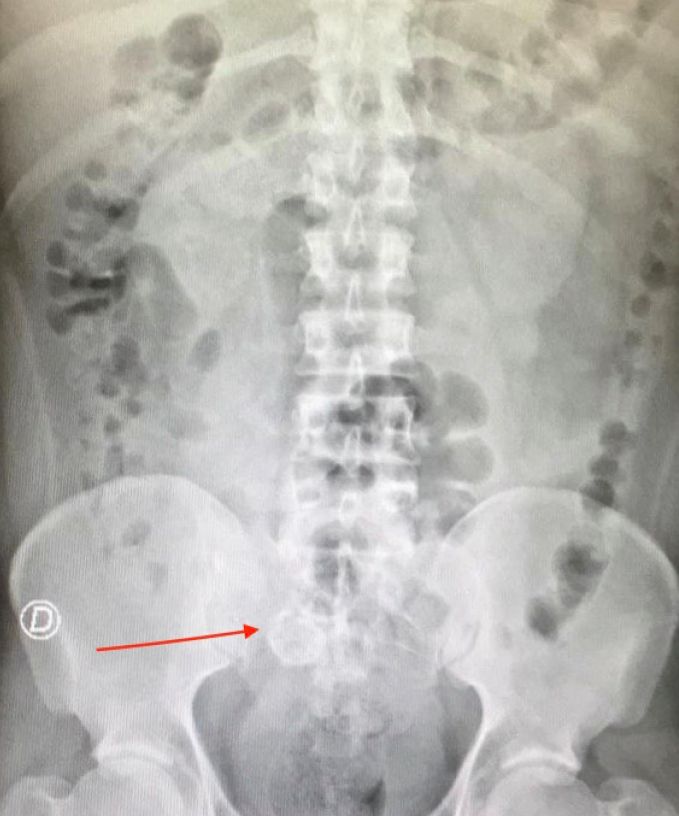

Q.7. What's the xray finding?

Correct Answer : B